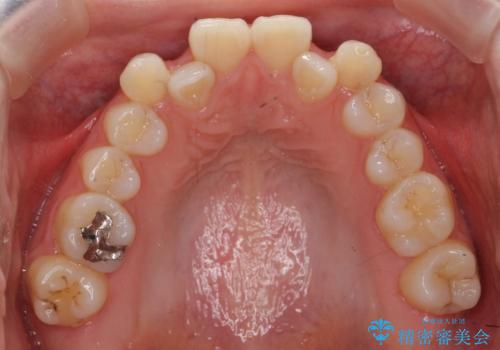

30代女性 前歯のがたつき